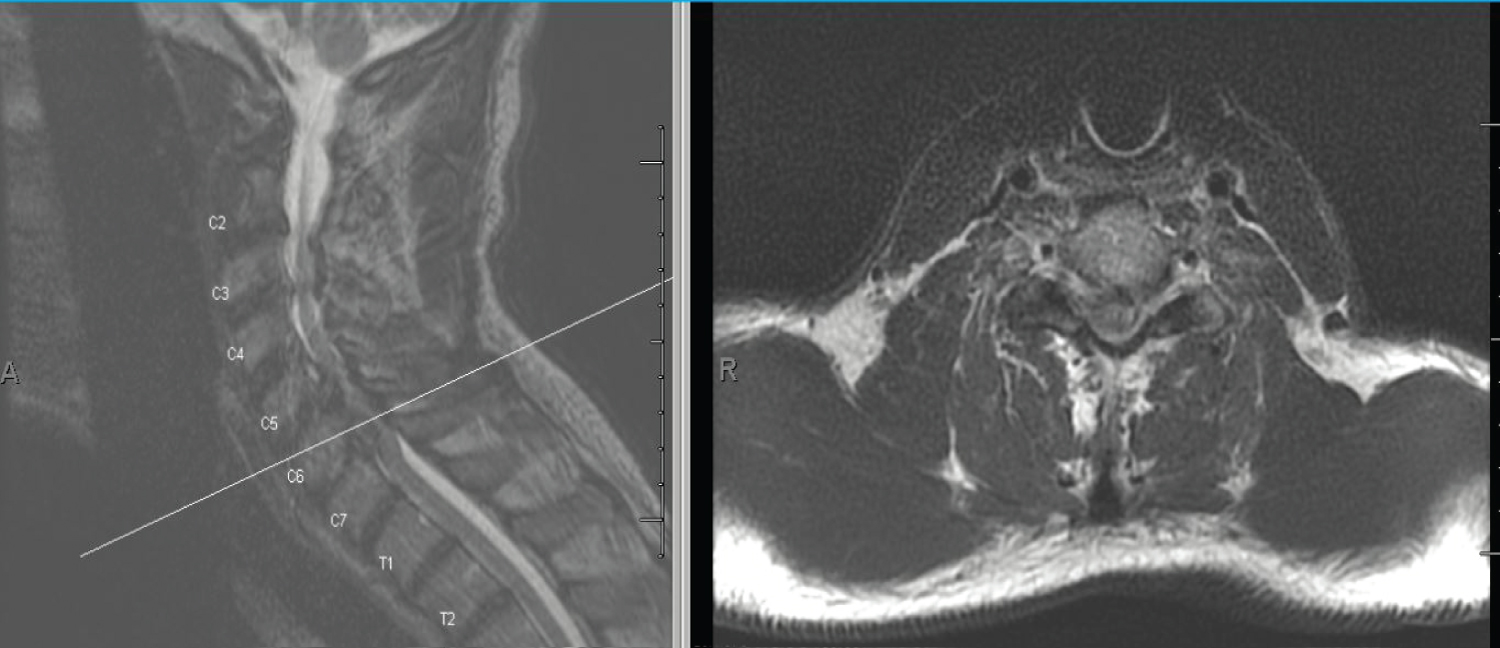

The patient initially presented to emergency department with progressive upper and lower extremity weakness. Physical exam revealed right greater than left upper and lower extremity weakness, radiculopathy and decreased sensation in bilateral upper extremities and hyperreflexia in the right lower extremity. Neurosurgery recommended MRI under sedation or CT myelogram, which the hospital does not perform. He was transferred to another facility with those capabilities. The patient presented to the ED with physical exam significant for signs of cervical myelopathy. He exhibited Hoffman's sign bilaterally, clonus in the right ankle, and hyperreflexia in upper and lower extremities bilaterally. Babinski was absent. Weakness in right hand and lower extremity was seen on motor exam (Table 2). MRI of the cervical, thoracic, and lumbar spine were performed under sedation. It displayed severe cervical degenerative disease spanning from C2-C7, ossification of the posterior longitudinal ligament of the C5-C6 segment, and severe spinal canal stenosis with moderate to severe cord compression from C5-C6, C6-C7 (Figure 1 and Figure 2). Two hours after the initial MRI, the patient developed sudden onset right leg plegia and worsening motor weakness in his right hand (Table 3). A repeat MRI was performed and revealed a hyperacute hemorrhage surrounding the extruded C6-C7 disc was revealed through T1 weighted imaging. The patient underwent an emergent anterior posterior cervical decompression fusion involved laminectomy's from C3-7 and a posterior fusion with pedicle screws from C2-T1 (Figure 3). On postoperative day 6, there was some improvement in neurology, with a returning of lower extremity strength from 0/5 to 4/5 (Table 4). During a follow-up of 3 months after discharge, the patient reported relief of pain and full return of sensory and motor deficits.

Figure 1: MRI of cervical spine shows a massive disc herniation at C6-C7 causing severe central canal narrowing. There is ossification of the posterior longitudinal ligament at C4-C6. 2 small foci of T2 signal hyperintensity in the left dorsal aspect of the cord at C5 level. View Figure 1

Figure 2: MRI of cervical spine shows a massive disc herniation at C6-C7 causing severe central canal narrowing. Cross-section. View Figure 2